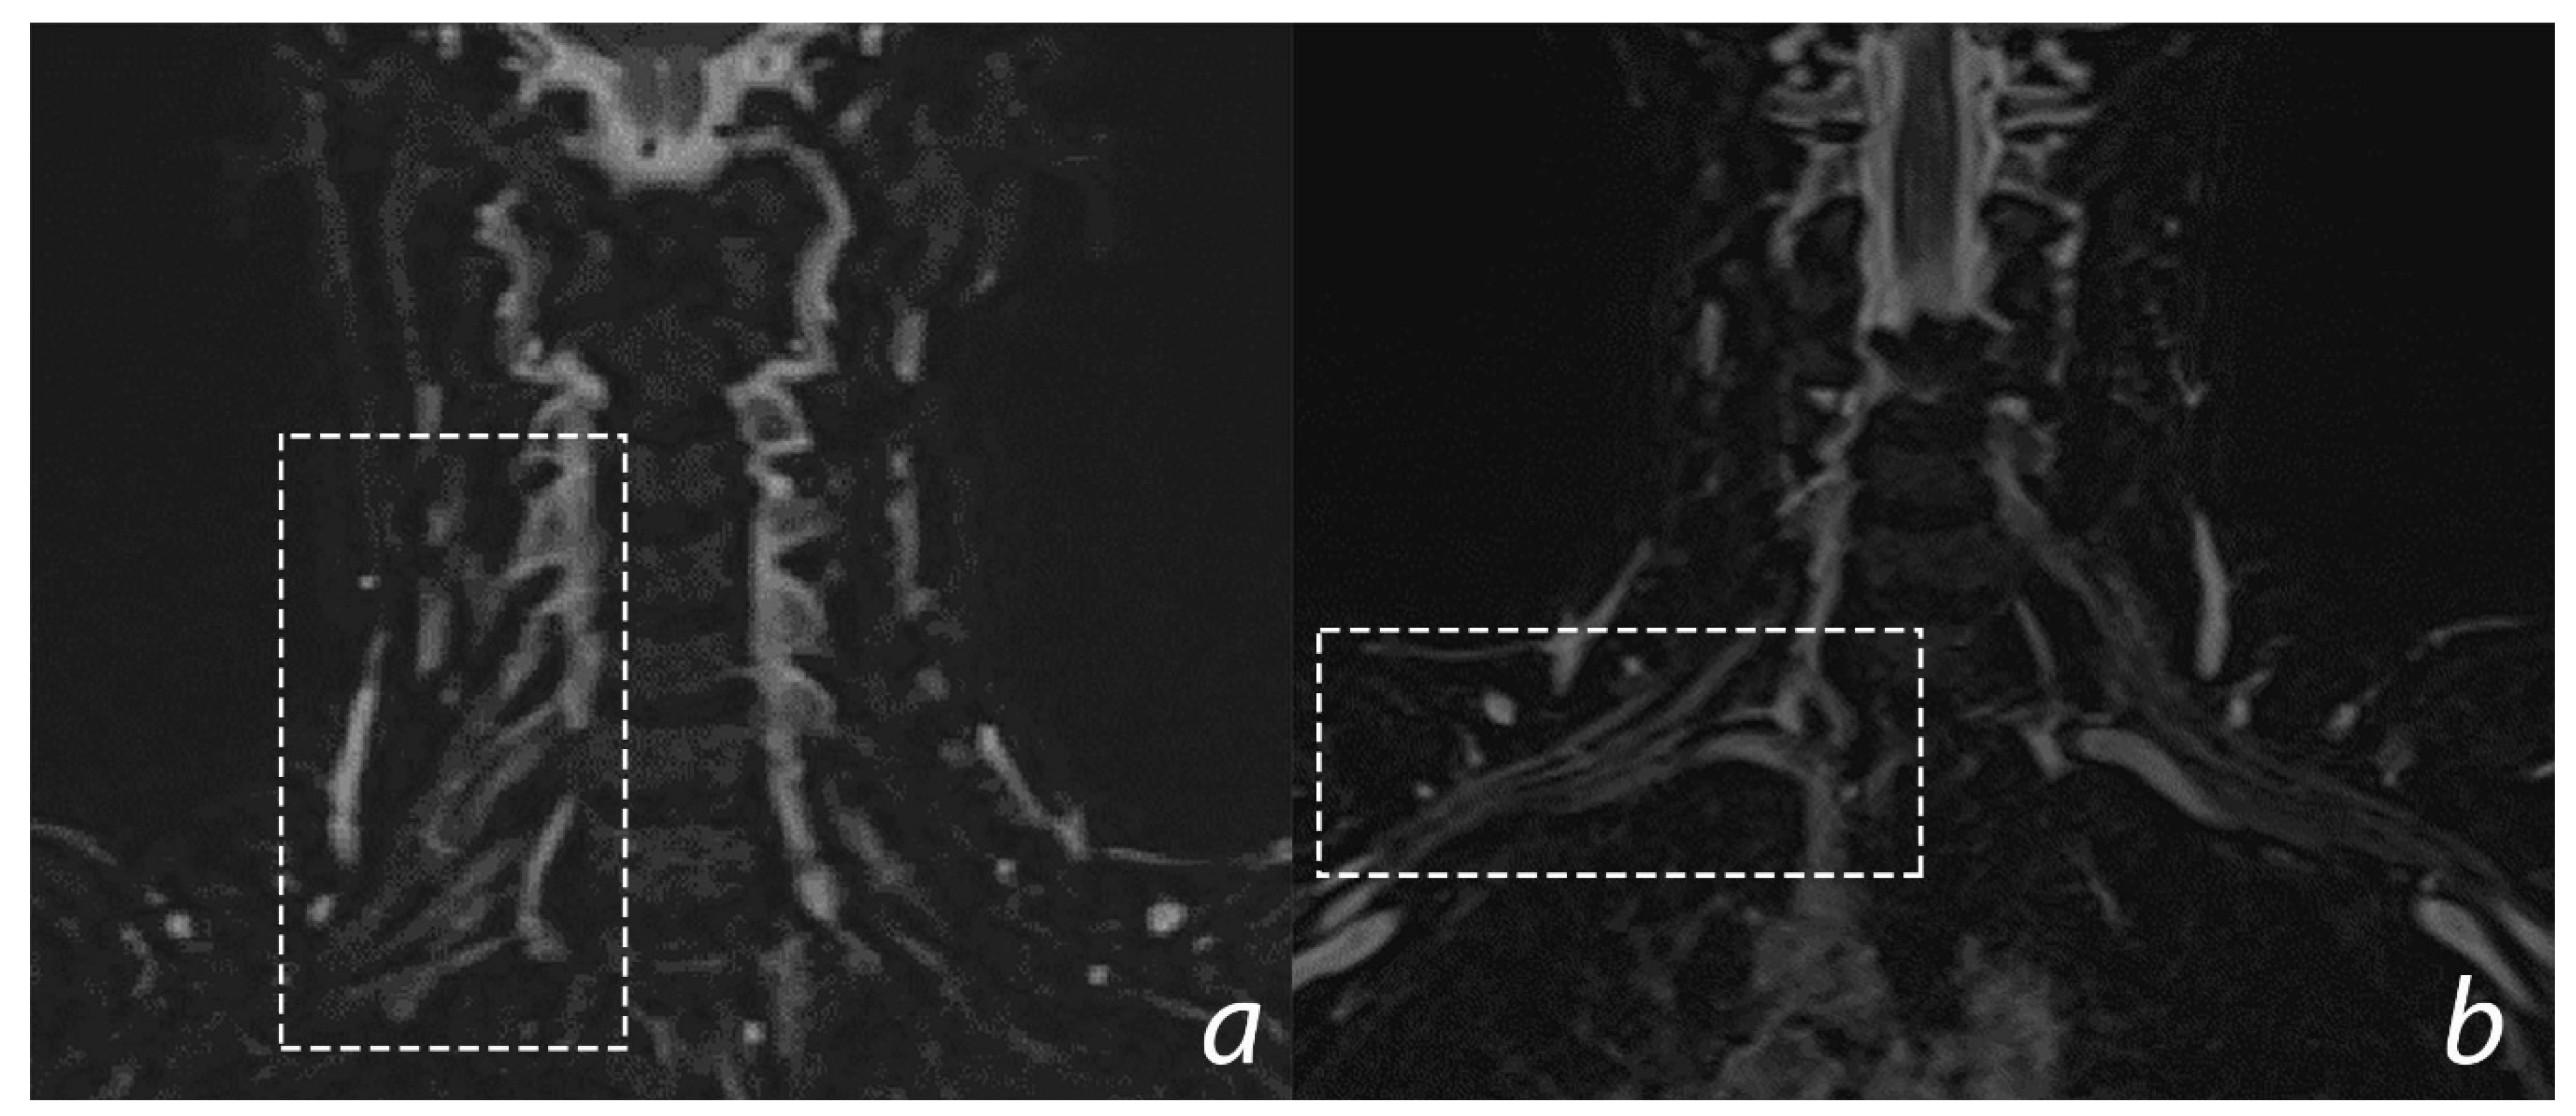

Imaging techniques to investigate peripheral nerves have become more common in the last few years. Indeed, improvements in the equipment allow better investigation of these structures. X-ray and MRI of the cervical spine are commonly performed and are useful to rule out vertebral fractures, spinal cord involvement, and to assess some indexes like the Mean Subaxial Cervical Space Available for the Cord (MSCSAC): the antero-posterior diameter of spinal canal minus the antero-posterior diameter of spinal cord, measured in a sagittal plane. Indeed, some previous results showed an association between risk of BPIs and cervical canal stenosis assessed through this method in athletes [75]. Modern magnetic resonance (MRI) is useful to define the nerves and their relationship with normal or pathological surrounding structures [76]. Nowadays, MRI could provide visualization and investigation of brachial plexus structures directly and could give some information about the neurogenic muscular changes, like denervation (Figure 3).

Figure 3.

3D T2 STIR SPACE sequence—coronal images of normal Brachial Plexus. (a) Dotted rectangle includes cervical spinal nerves emerging from the intervertebral foramina in the supraclavicular laterocervical region; (b) dotted rectangle includes the brachial plexus structures passing through the cervicoaxillary canal.